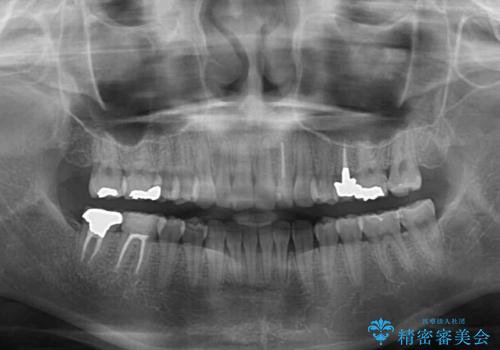

- 前歯が気になるとのことで来院された患者様です。

歯列不正は軽微であったため、インビザライン・ライトにより、費用を抑えて矯正治療を行うこととしました。

短期間で気になる前歯の歯列を改善することができました。